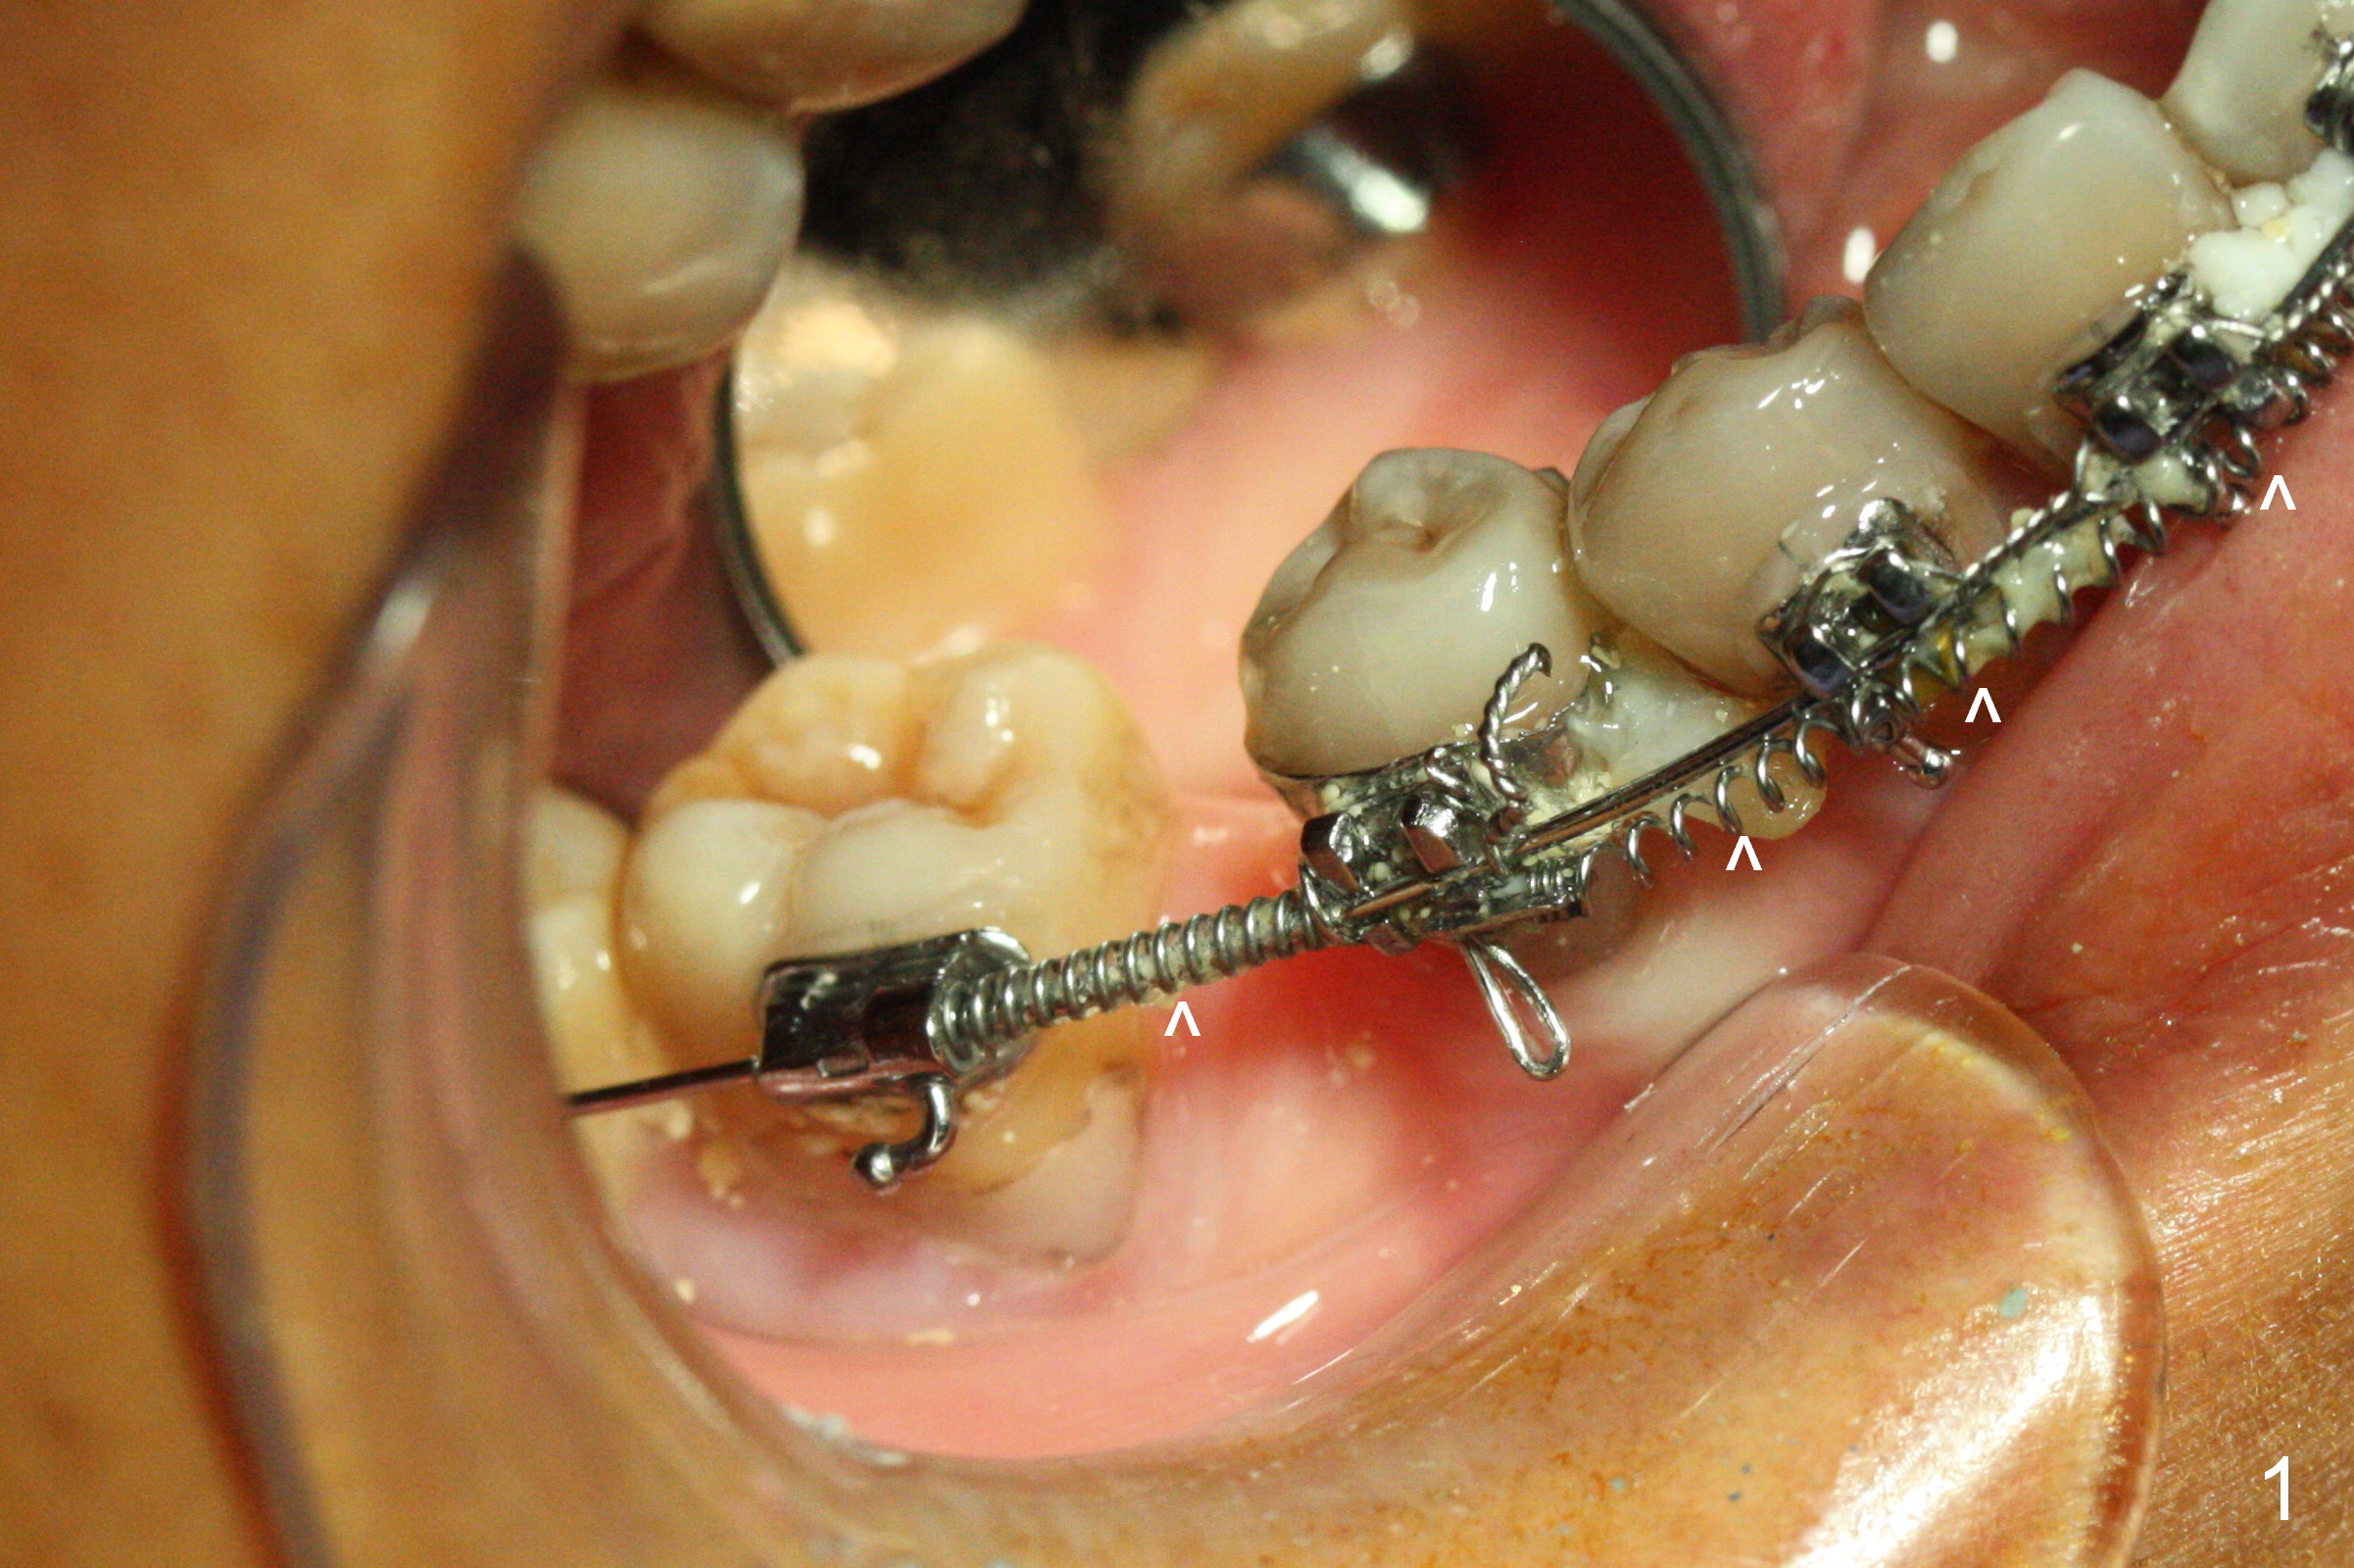

Mesialization of the tooth #29 consists of open coil spring distal (Fig.1 ^) and closed coil spring mesial (^^^). Due to limited time and incompliance, the mesialization is incomplete (Fig.3 *). Total treatment lasts 1 year. The mesial surface of the #29 (Fig.3 <) and the distal surface of #31 are trimmed before incision. The mesiodistal width increases from 5 mm to 6 mm. In fact the ridge is not too narrow buccolingually when an incision is made (Fig.3). There is bone buccal and lingual to a 2.5 mm osteotomy (Fig.3) after adjustment of its initial one with 1.2 mm pilot drill (Fig.2 (red dashed line: the Mental Loop). A 3x12(2) mm 1-piece implant is placed (Fig.4) with insertion torque > 40 Ncm. GBR is also done to increase ridge width.